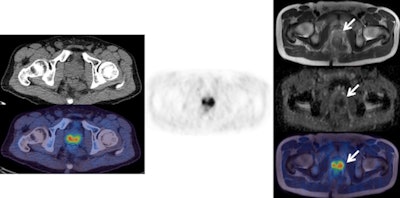

Left: F-18 choline PET/CT (CT top and fused PET/CT bottom). Center: F-18 choline PET. Right: MRI (from top to bottom: T2, ADC map, fused PET/T2 MRI). The images clearly show abnormal choline activity in a large prostate cancer. However, the CT image does not allow any anatomical definition of the local extent of the tumor. The higher tissue contrast on the T2 MRI allows better definition (arrow) of the organ confined cancer, correlating with choline uptake on the fused PET/T2 MRI scan, and confirms restricted diffusion on the ADC map.Beyond oncology, PET/MRI holds considerable promise in the diagnosis and care of neurological and cardiac patients, providing key data on what is taking place within organs and clues on whether therapies are working.